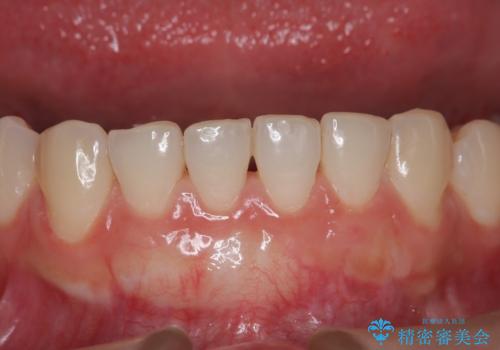

下顎前歯の歯肉退縮 結合組織を用いた根面被覆

十分な根面被覆を達成で患者様にも満足していただけました。